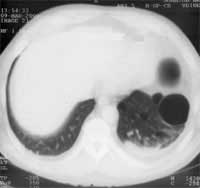

Точность же РКТ в диагностике этого заболевания значительно выше (Рис. 1б). При квалифицированно проведенном исследовании КТ позволяет выявить буллезные изменения легочной паренхимы в 100% случаев.

Рис. 1. (б) На компьютерной томограмме того же больного хорошо видна тонкостенная полость. В паринхиме обоих легких так же тонкостенные буллезные полости.

При гигантских буллах КТ дает возможность проследить их тонкую стенку и таким образом отвергнуть подозрение на спонтанный пневмоторакс.